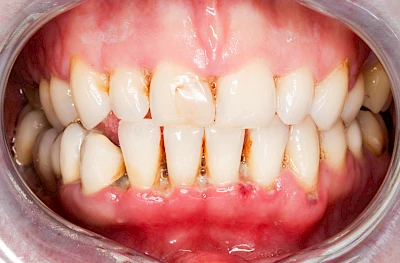

Bakterien in den Zahnbelägen greifen neben den Zähnen auch das Zahnfleisch (Gingiva) und den gesamten Zahnhalteapparat (Parodont) an. Der Körper reagiert mit einer Entzündung, sichtbar als Rötung und Schwellung. Meist blutet das Zahnfleisch z .B. beim Essen oder auch beim Putzen der Zähne.

Gingivitis & Parodontitis: Stadien

Ist zunächst nur das Zahnfleisch von der Entzündung betroffen, spricht man von Gingivitis. Später, wenn auch der Knochen um die Zähne herum entzündet ist, spricht man von einer Parodontitis. Bei der Parodontitis wird der Knochen nach und nach abgebaut und das Zahnfleisch zieht sich zurück. Die Zahnhälse und Zahnwurzeloberflächen liegen mehr und mehr frei. Die Zähne werden zunehmend lockerer und fallen schließlich aus.